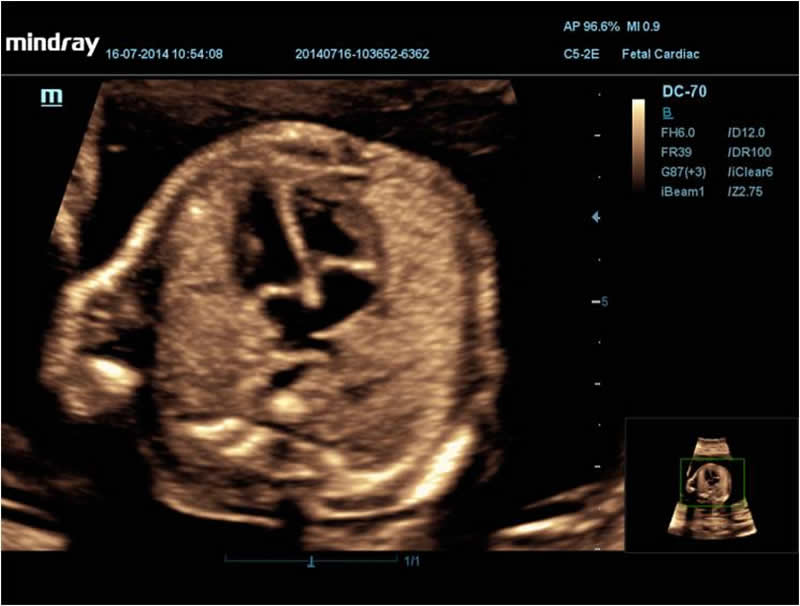

Рот эмбриона, 3D

Сердце эмбриона